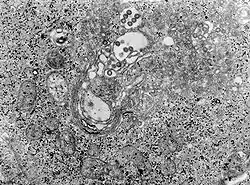

![]() micrografía MET de tejido infectado con el virus de la fiebre del valle del Rift | ||